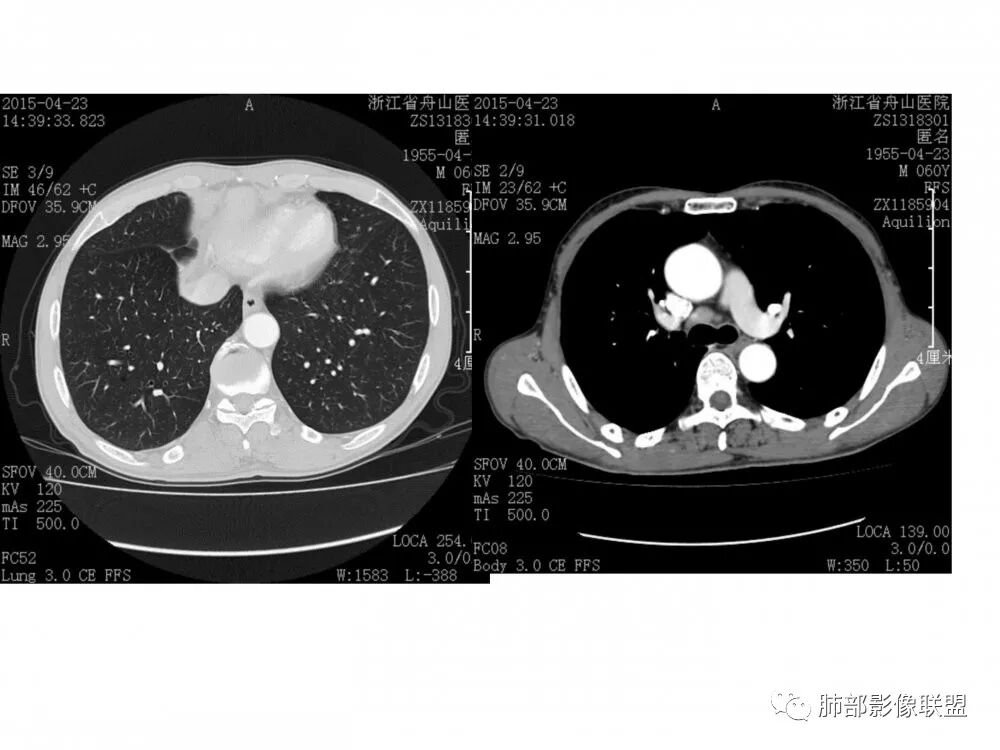

右肺下叶支气管不规则软组织肿块,病灶沿支气管生长,有一定的张力,部分包绕支气管壁,增强病灶内可见中度强化,内部有延迟强化的特点,周围淋巴结增大,诊断恶性病变无疑,远端无明显支气管阻塞,主要考虑粘液表皮癌,腺样囊腺癌,鳞癌之间鉴别,病灶有类似神经源性病变生长方式,腺样囊腺癌,其次考虑鳞癌或粘液表皮癌。

支持腺样囊性癌,老年男性,支气管肿块,横径大,轻度不均匀强化,小血管受侵模糊,纵隔肺门多发肿大淋巴结。代排黏液表皮癌,一般年轻人,强化更轻。鳞癌,无阻塞性肺炎不太支持,小细胞癌及不典型类癌放后面考虑

右肺门结节,内见包埋血管,不均匀强化,长轴沿支气管且围绕支气管生长,支气管受压狭窄而未阻塞,肺门及纵隔见肿大淋巴结,老年男性,似有肺气肿背景,考虑恶性肿瘤性病变,首选小细胞肺癌

右肺下叶支气管开口新生物,轴位管腔及纵向基底干大部分受累狭窄,支气管管壁破坏并突破形成腔外肿块,血管累及变细,肉眼观轻度强化,右肺门、纵膈淋巴结肿大,恶性没问题,阻塞性炎症不明显,类癌强化明显不支持,老年男性,首先考虑小细胞癌,鉴别不典型鳞癌和腺癌。

右肺下叶开口支气管内新生物,破坏管壁向腔外膨胀生长,累及各基底段开口,无明显坏死,有局部强化,远端无明显阻塞,右肺门及纵隔淋巴结肿大,考虑恶性肿瘤。大气道肿瘤不支持腺癌。小细胞癌大多为周围病灶引起肺门、纵隔淋巴结转移,肺门淋巴结明显肿大后侵犯支气管粘膜到达支气管内(从外到内),本例病灶从管腔内向腔外长,不支持小细胞癌。病灶为轻→中度强化,类癌显著强化为主→不支持,鳞癌、腺样囊性癌一般中度强化,鳞癌大多有阻塞性病变,本例无明显阻塞不支持鳞癌。粘液表皮样癌一般为轻度不均匀强化。感觉病灶为轻中度不均匀强化。综上首先考虑粘表,其次腺样囊性癌。待支气管镜活检明确。